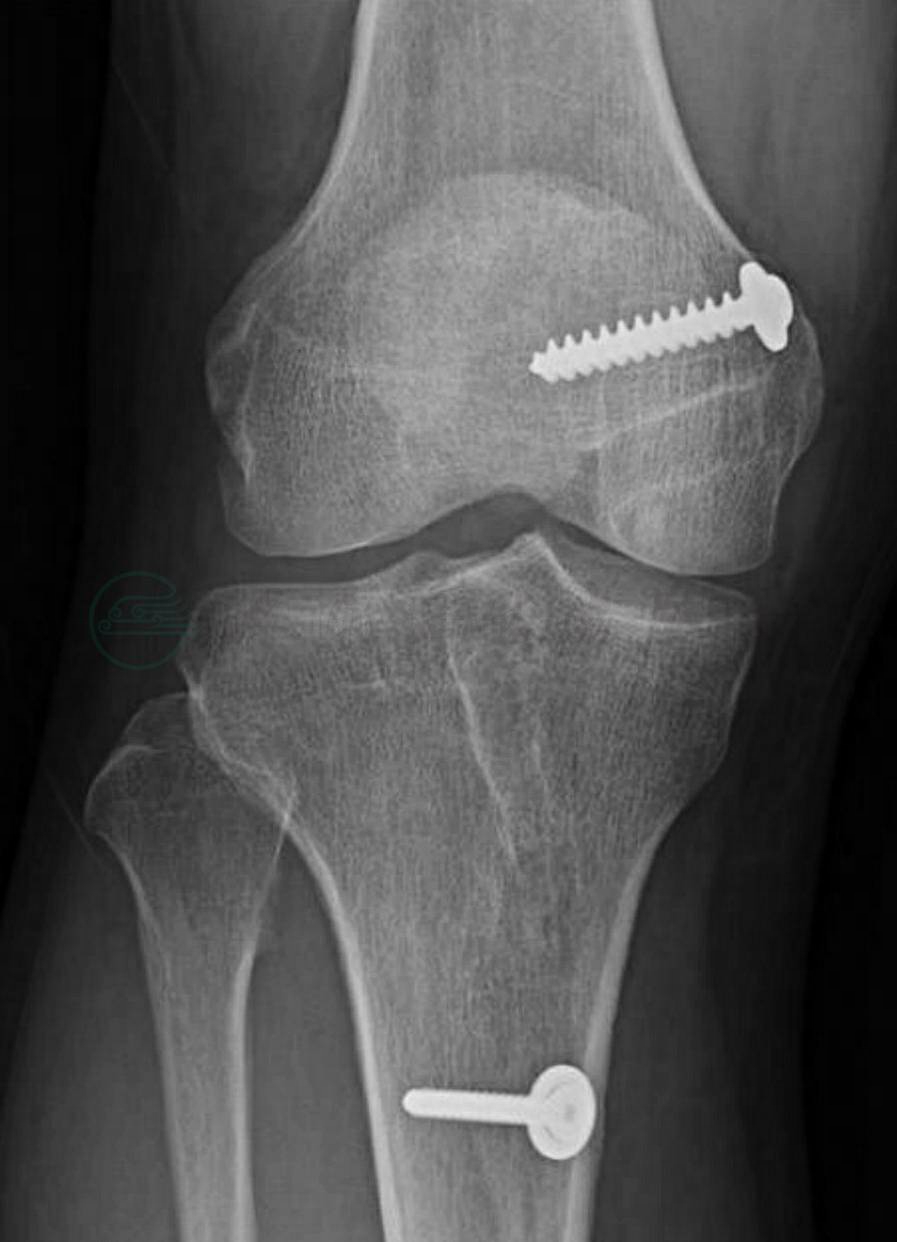

图1 后十字韧带撕裂后膝关节松弛

后十字韧带撕裂通常会被误诊,因为其临床症状轻微,甚至没有症状。其损伤机制通常为屈曲位胫骨近端前方受力所致,向后且合并内翻或旋转的外力可能会导致外侧或后外侧的联合损伤。另外一种导致单纯后十字韧带损伤的机制为膝屈曲着地的同时伴踝关节的跖屈。其他损伤机制包括极度过伸或过屈。单纯的后十字韧带部分撕裂或全部撕裂可以保守治疗,短期疗效良好,长期疗效尚有争议。后十字韧带的手术效果则很难说。最新的解剖和生物力学研究表明,手术重建适用于有症状的严重膝关节后侧不稳定或多韧带损伤。在考虑后十字韧带治疗方案的时候,要考虑以下因素:疼痛程度、不稳定程度、急性还是慢性损伤、MRI 检查结果、单一损伤还是复合损伤、患者生活方式是积极的还是消极的等等(图2)。